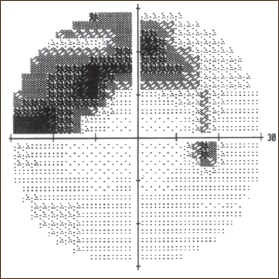

► If the loss is nasal or binasal, the deficit is either retinal, in the optic nerve or possibly optical. The most common source is glaucoma (see Figure 1, page 28), but one must look at the pattern of visual loss to get a clear idea, as described below.

Figure 1: Grey scale representation of a glaucomatous visual field defect.